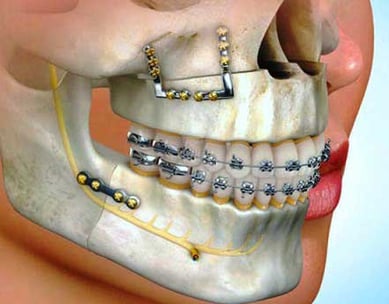

Surgical Orthodontics

For complex cases involving jaw discrepancies, surgical orthodontics may be necessary. Our team collaborates with oral surgeons to correct these issues, enhancing both function and facial aesthetics.